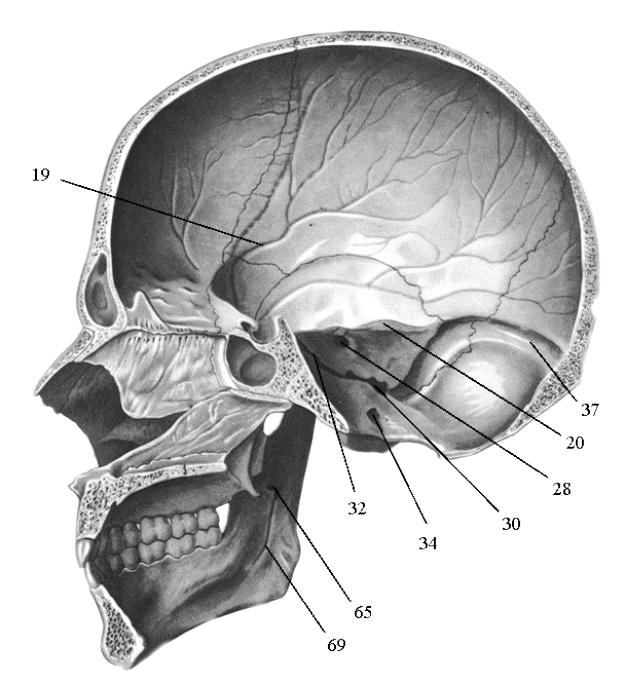

Анатомические изображения срединной сагиттальной линии черепа